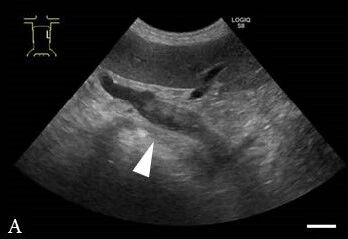

第79天,情况稳定。腹部超声显示PVT明显减少,直径降至7.12 mm(下图B)。确认了脾静脉扩张消失。利伐沙班明显改善了PVT和SVT,但由于经济和时间限制,主人希望停止使用利伐沙班。因此,利伐沙班被替换为氯吡格雷(2.5 mg/kg,PO,q24h),并开具了泼尼松龙、螺内酯和熊去氧胆酸,疗程为1个月。

↑ (B) 在第79天观察到门静脉扩张和血栓(白色箭头)的直径显著减少,直径与第14天相比减少到65%。